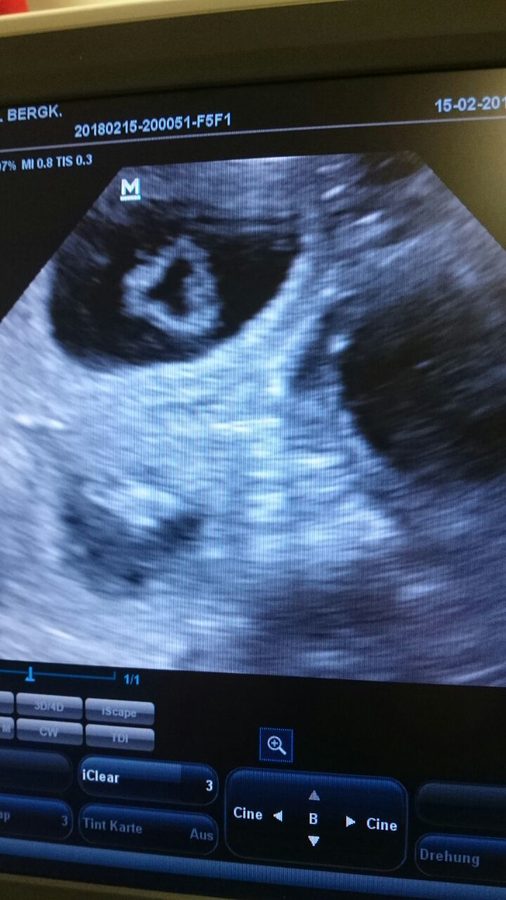

YUHUU, Fayola ist trächtig und wir erwarten unseren A- Wurf um den 20.03.2018!!!